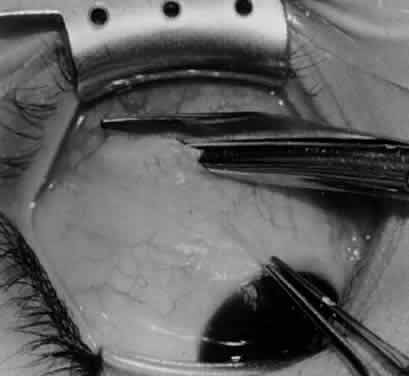

Fig. 18. The final position, with the inferior oblique muscle recessed 10 mm. The inferior rectus muscle is retracted with a Green muscle hook. As described in the text, the 14-mm recession would place the inferior oblique muscle over the inferior temporal vortex vein, and the 6-mm recession would place the inferior oblique muscle anterior and nasal to this position.

Fig. 19. A 14-mm inferior oblique muscle recession is placed over the inferior temporal vortex vein.

Fig. 20. Optional closure of the incision with a 6-0 Vicryl suture. The incision may be allowed to heal without a suture.